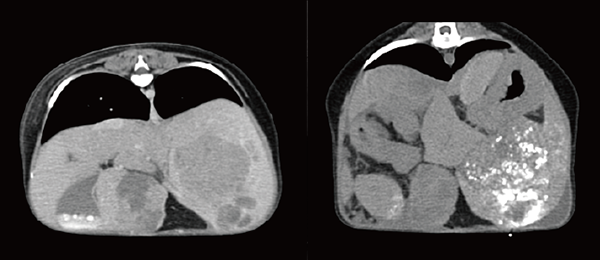

4. 종양 중재치료

동맥혈관을 통해서 종양에 분포하는 혈관으로 항암약제의 직접 주입과 색전물질 주입으로 암세포를 사멸시키는 치료법입니다. 종양 초기 환자부터 수술적 적출이 불가능한 난치성 암환자까지 적용이 가능하며, 비수술적으로 암을 치료하는 최신 치료법입니다. 환자 상태에 따라서 동맥항암요법, 동맥색전술, 동맥색전화학술 등을 조합하여 선택적 치료를 진행하게 됩니다.